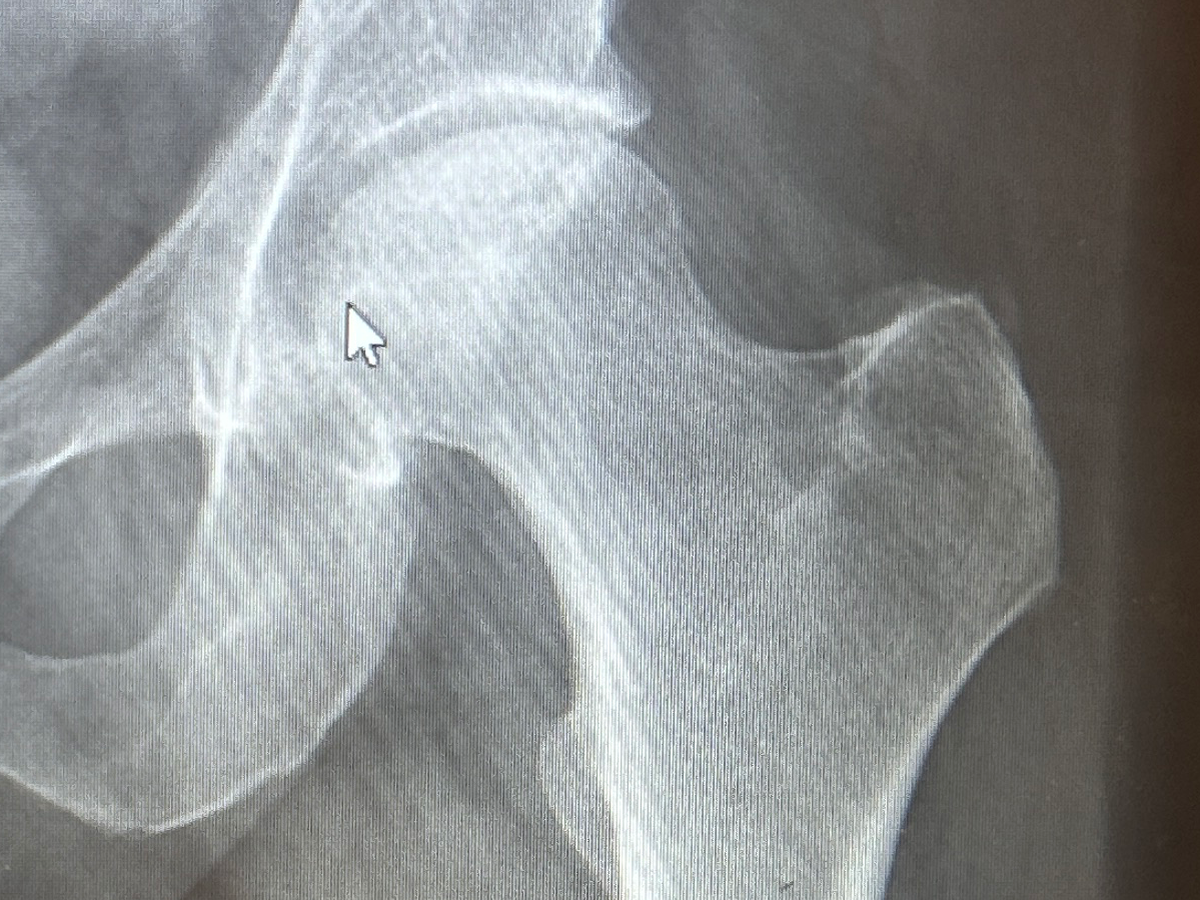

I need help covering the shortfall in income from short-term disability payments after a total hip replacement. This will be my second THR from bilateral avascular necrosis of my femoral heads. My right hip was replaced in February, and the intention had been to wait until next year for my left to be replaced, but it’s not holding up as hoped. I am the sole source of income for our family of five, with my wife staying home with our three children, ages 9, 13, and 15 and homeschooling them. Unfortunately my previous surgery has caused a denial in supplemental short term disability coverage, and the maximum payment is less than $500 a week. That is less than half of what a normal income would be each week.

For those curious, avascular necrosis is the death of bone matter due to restricted or loss of blood flow to a portion of the bone. It is most typically found in long bones like a femur. There is no cure except a hip replacement. Most often it is only diagnosed in the late stages when the pain becomes severe, and when a patient has an X-ray or other scans done. At that stage, the only option is the surgery, with intermittent subcutaneous corticosteroids injections as a layover until surgery can be scheduled.